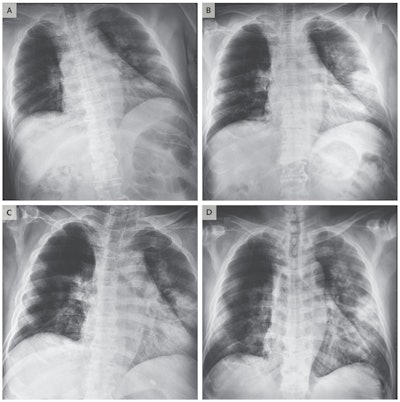

Chest radiographs obtained at admission (A) and on day 3 (B) of man who had traveled to Wuhan. Image C was acquired on day 5 and image D on day 6. Images courtesy of New England Journal of Medicine.Samples were collected from the man with throat swabs; they tested positive for 2019-nCoV on reverse transcription polymerase chain reaction (RT-PCR) diagnostic assays. The man was then admitted to the hospital, where he was treated with antiviral medications, broad-spectrum antibiotics, and other therapies.

Chest radiographs were also acquired, indicating an infiltrate in the upper lobe of the left lung. The man received supplemental oxygen because of increasing dyspnea with hypoxemia, and a progressive infiltrate and consolidation were observed on the chest x-rays.